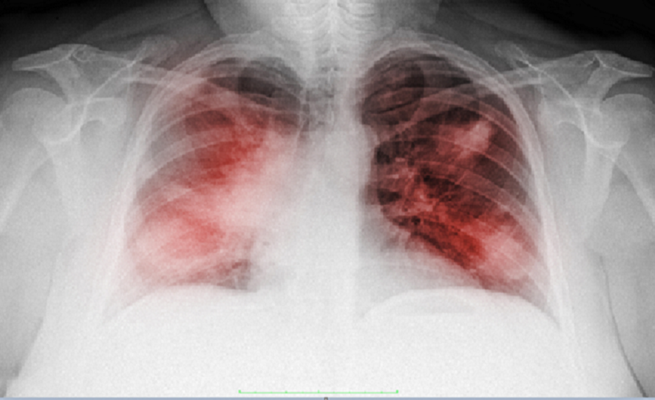

الكشف عن فيتامين يمكن أن يدمر خلايا سرطان الرئة

اكتشف علماء جامعة موسكو أن جرعات عالية من فيتامين В1 تؤثر سلبا في خلايا سرطان الرئة، دون أن تلحق أي أضرار بالخلايا السليمة.